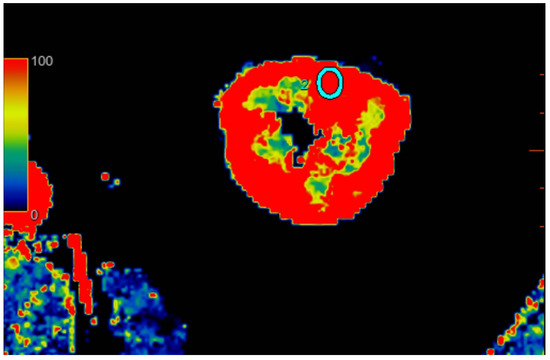

2.2.2. Quantitative Analysis of Perfusion

2.3. Kidney Ultrasound